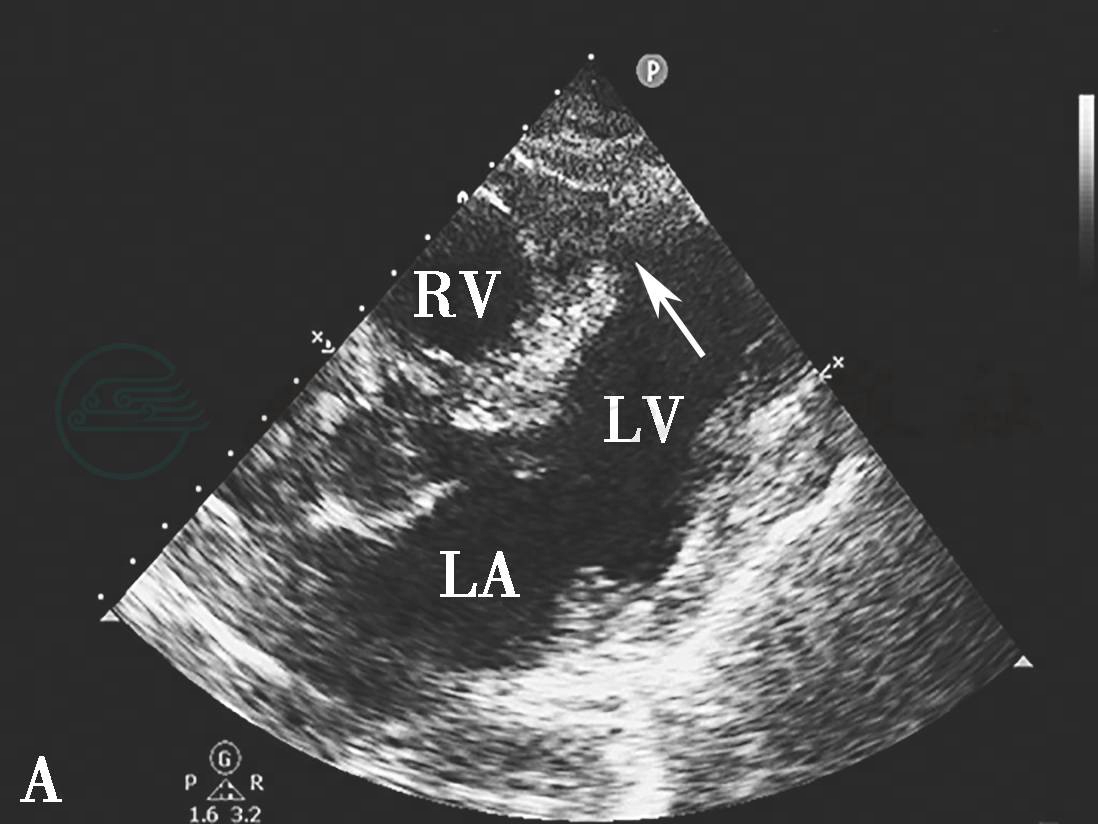

图3心肌梗死后室间隔穿孔二维切面图像

A.胸骨旁四腔切面显示室间隔心尖部连续中断(箭头示);B.二尖瓣短轴切面显示后间隔基底部连续中断(箭头示)。LA.左心房;LV.左心室;RV.右心室。